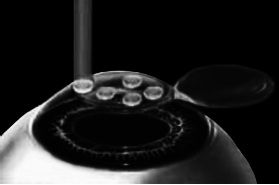

После формирования роговичного лоскута убирают инструменты микрокератома, затем шпателем откидывают его вбок (рис. 5). Обнажается роговичное ложе, то есть место, на котором лежал лоскут. Это верхние слои стромы роговицы. Ложе осушают тупфером и так же, как и при ФРК, настраивают лазер и испаряют несколько микрон вещества стромы (рис. 6). Потом промывают строму водой и шпателем укладывают лоскут на место.

Рис. 5. Роговичный лоскут откинут в сторону.

Иллюстрация с сайта Международного лазерного центра www.optics.ru

Рис. 6. Луч эксимерного лазера испаряет на роговичном ложе несколько микрон стромы роговицы.